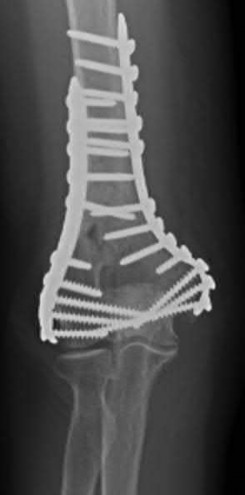

Question 19:

A 28-year-old male sustains a closed comminuted tibial shaft fracture. Two hours post-injury, he develops severe leg pain unyielding to narcotics. His blood pressure is 120/80 mmHg. Intracompartmental pressure monitoring is performed. Based on current guidelines, which measurement dictates an emergent 4-compartment fasciotomy?

Options:

- Absolute compartment pressure > 20 mmHg

- Absolute compartment pressure > 25 mmHg

- Delta pressure (Diastolic BP - Compartment Pressure) < 30 mmHg

- Delta pressure (Systolic BP - Compartment Pressure) < 30 mmHg

- Delta pressure (Mean Arterial Pressure - Compartment Pressure) < 40 mmHg

Correct Answer: Delta pressure (Diastolic BP - Compartment Pressure) < 30 mmHg

Explanation:

Acute compartment syndrome is classically defined by tissue hypoperfusion. The absolute compartment pressure is less reliable than the differential pressure (Delta P). A Delta P (Diastolic Blood Pressure minus Compartment Pressure) of less than 30 mmHg is an absolute indication for emergency fasciotomy, as capillary perfusion gradient is lost when tissue pressure approaches the diastolic pressure.